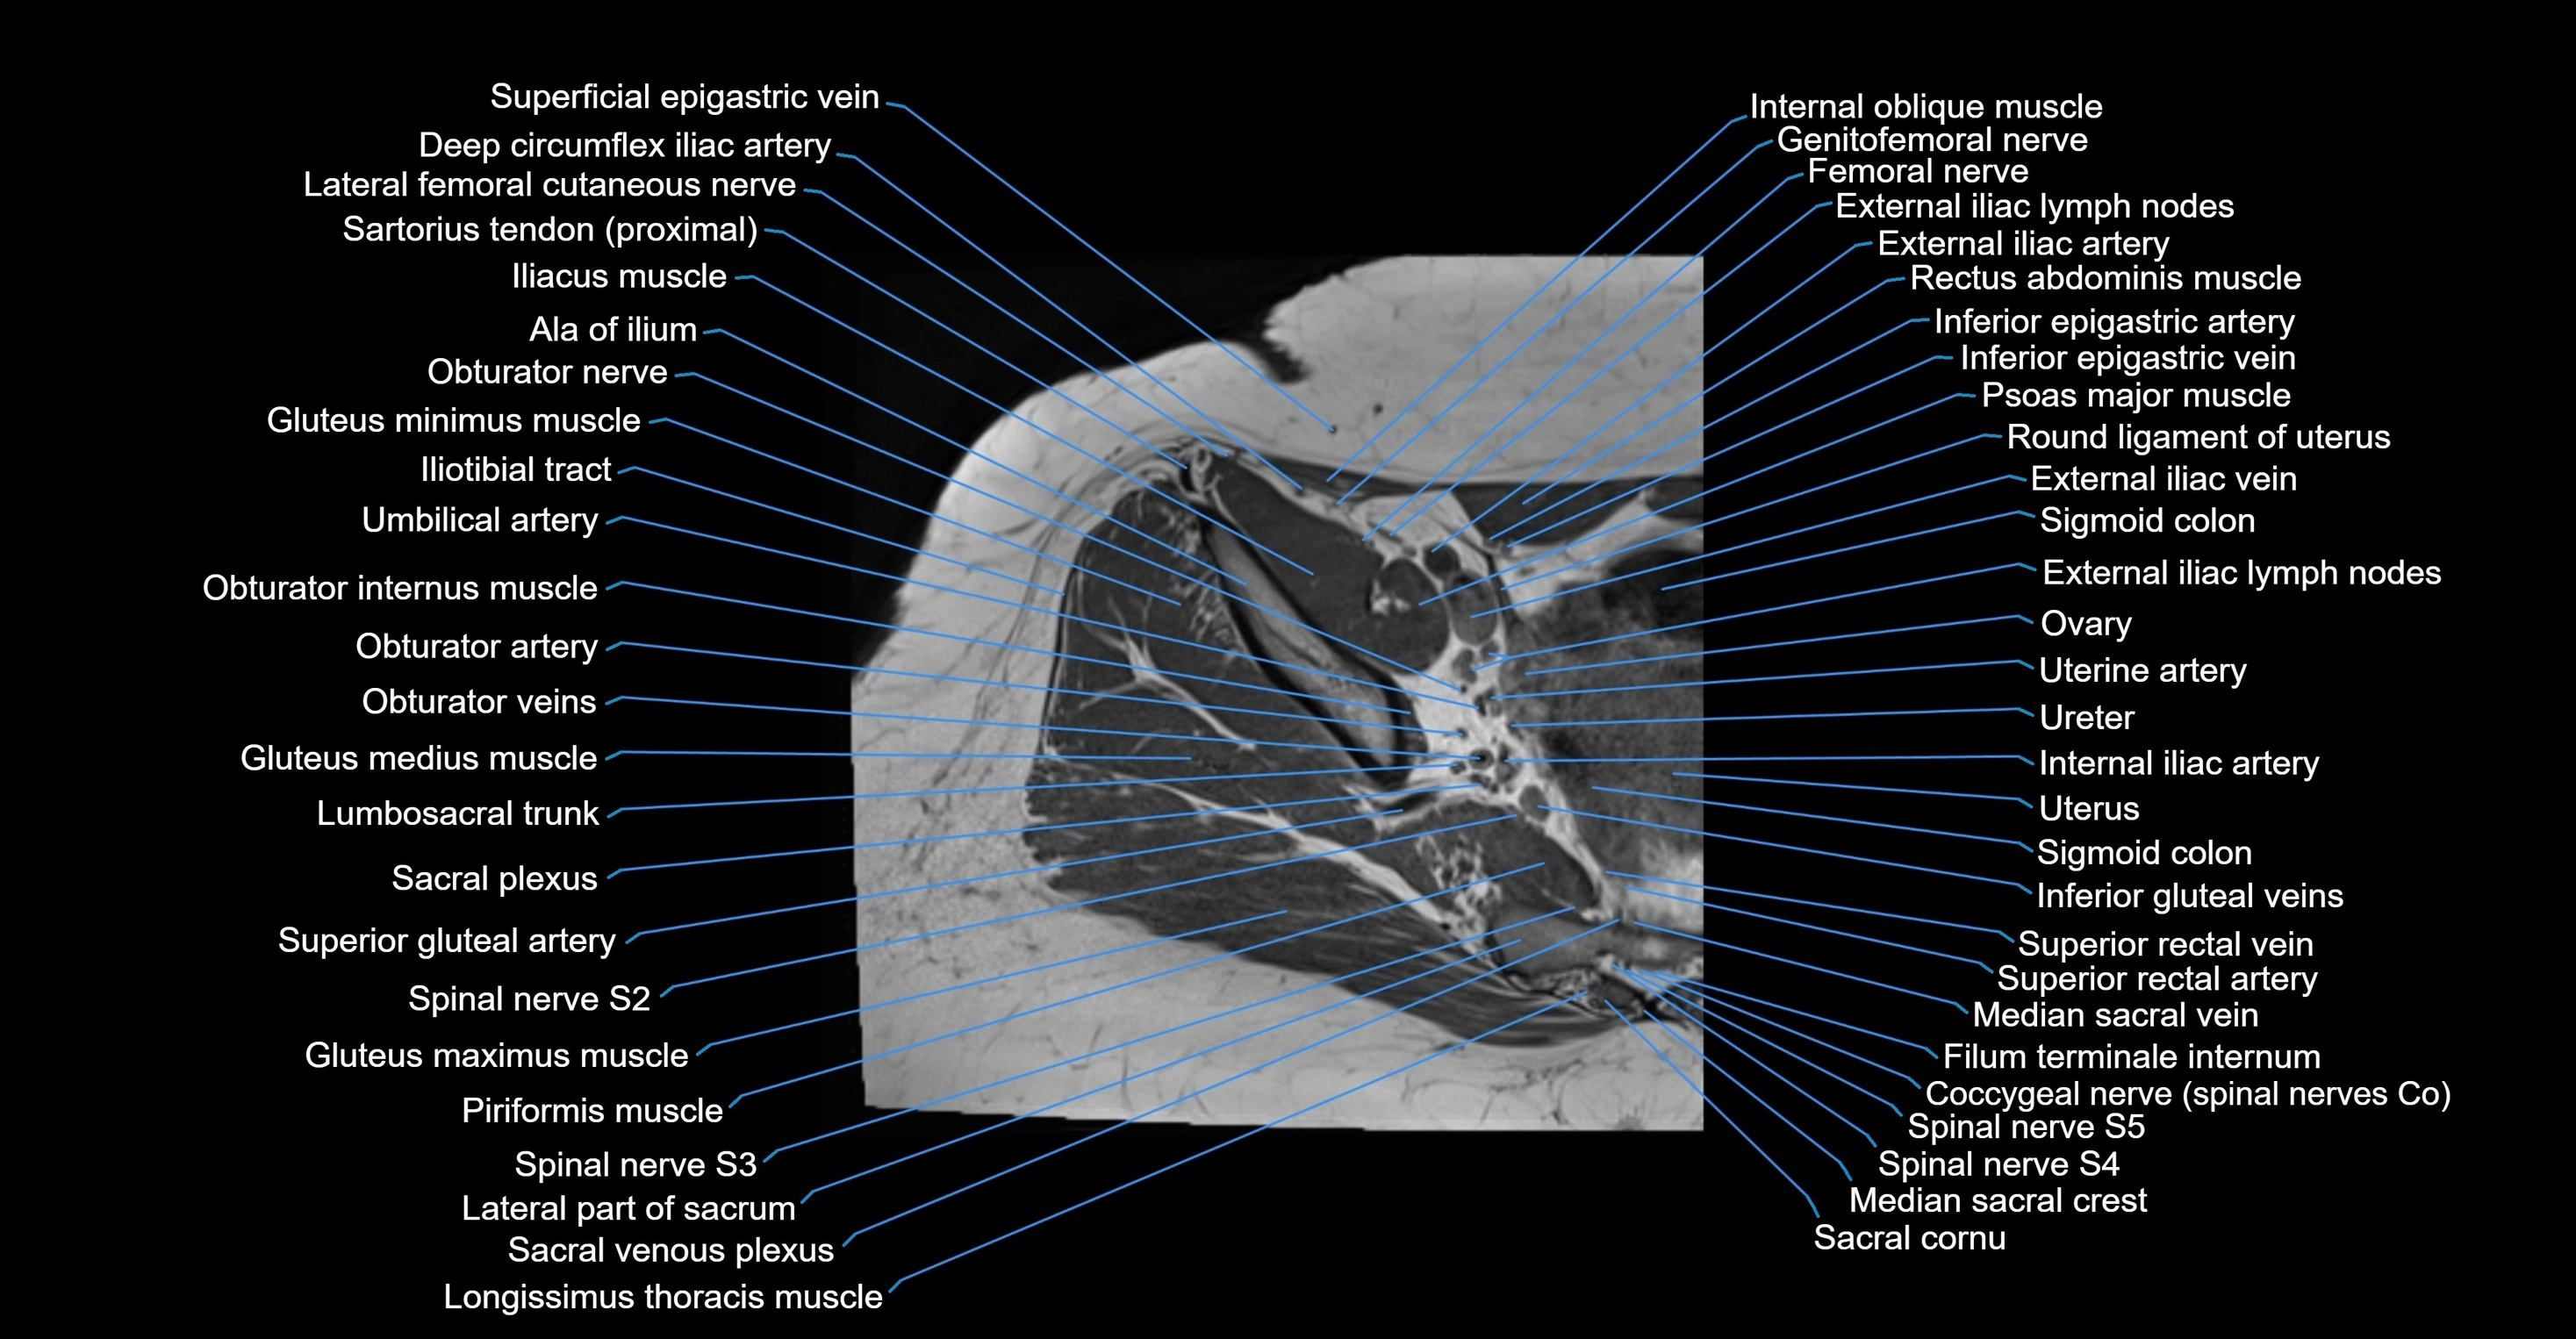

- External iliac lymph nodes

- External iliac vein

- Filum terminale internum

- Internal iliac artery

- Lateral part of sacrum

- Lumbosacral trunk

- Median sacral crest

- Median sacral vein

- Ovaries

- Round ligament of uterus

- Sacral plexus

- Sigmoid colon

- Spinal nerve S2

- Spinal nerve S3

- Spinal nerve S4

- Spinal nerve S5

- Superior gluteal artery

- Superior rectal vein